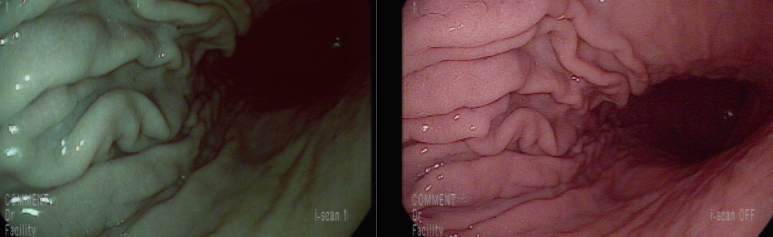

위각부 궤양

전반적인 만성 표재성 헬리코박터 위염 소견

십이지장의 구축으로 인한 협착 상태, 내시경 통과는 문제 없다.

1년전과 비교하면

위각부에 거의 아물어 있는 궤양 소견

기타 위와 같은 소견